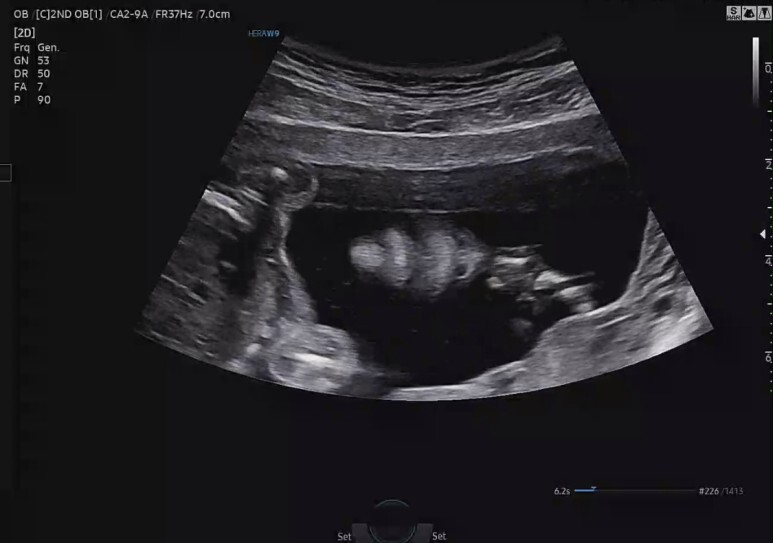

21주 +5일, 정밀 초음파

또 기다리던 4주가 지나고 정밀 초음파 검사.

정밀 초음파는 일반 초음파와 달리 초음파 검사실도 다르고, 20분 이상 길게 초음파를 봐야해서 미리 시간예약을 하고 늦지 않게 병원에 내원했다.

전체적으로 무난히 잘 자라주고 있다. 평균보다 살짝 작지만 괜찮아 :)

캡쳐한 부분 외에 초음파 선생님께서 나한테 굳이 설명할 필요 없는 부분들은 빠르게 슉슉 확인하고 지나가셨다.

초음파 시간은 총 15분 정도. 많이 길지 않아서 꿀잠이도 너무 스트레스 받지 않았을 것 같다.

초음파 보는 내내 꼼지락 거리는 것도 귀여웠고,

큰 이상 없이 다 잘 자라주고 있다니 너무나도 감사한 마음.